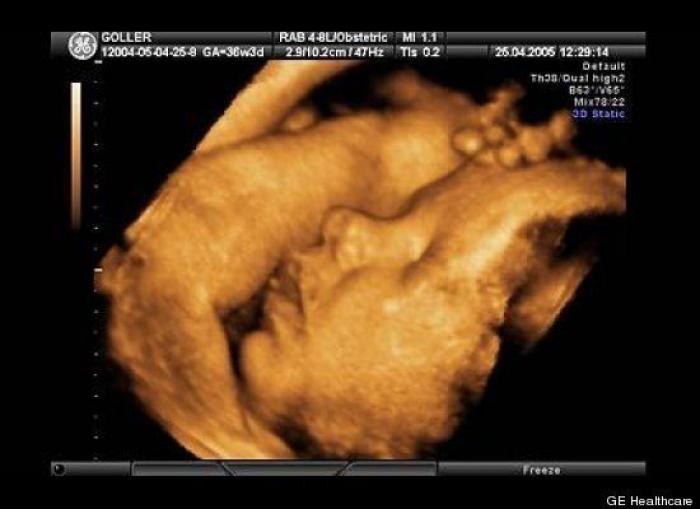

En esta galería puedes ver en fotos como es el desarrollo de un feto de semana en semana:

Desarrollo del feto, en fotos